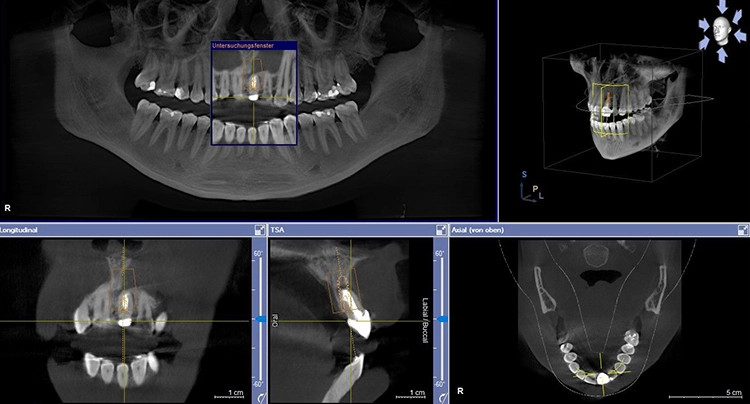

In Vorbereitung auf die Implantatplanung und das CAD/CAM-Herstellen der temporären Krone erfolgte eine digitale Datenerfassung mit dem Intraoralscanner (Trios 3, 3Shape). Der Datensatz der Ausgangssituation sollte später bei der CAD-Konstruktion hilfreiche Informationen liefern (Abb. 3). Mit dem Scan ist die Ausgangssituation digital archiviert und steht jederzeit zum Abruf bereit. Zudem wurde ein DVT für die Planung der Implantatposition am dreidimensionalen Bild vorgenommen und der DICOM-Datensatz in die Implantatplanungssoftware importiert (Abb. 4 und 5).

Theoretisch kann in der Planungssoftware der STL-Datensatz aus dem Intraoralscanner (Ausgangssituation oder Set-up) hinzugezogen und so die Implantatposition aus prothetischer Sicht ideal definiert werden. Im vorgestellten Fall ergab die 3D-Diagnostik ein ausreichend stabiles Knochenvolumen in regio 21. Geplant worden ist die Insertion eines BLX-Implantates (Straumann).